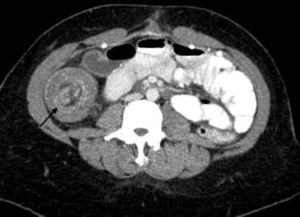

Adult intussusception is a rare entity, accounting only for 1% to 5% of cases of bowel obstruction.

Fundic gland polyps are the most common form of gastric polyps. Giant FGPs, however, are extremely rare.